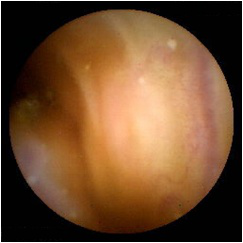

②结肠镜

结肠镜可以观察包括直肠、乙状结肠、降结肠、 横结肠、升结肠、盲肠至回肠末端的肠道黏膜,主要用于诊断结、直肠炎症,良性肿瘤,息肉,憩室等疾病